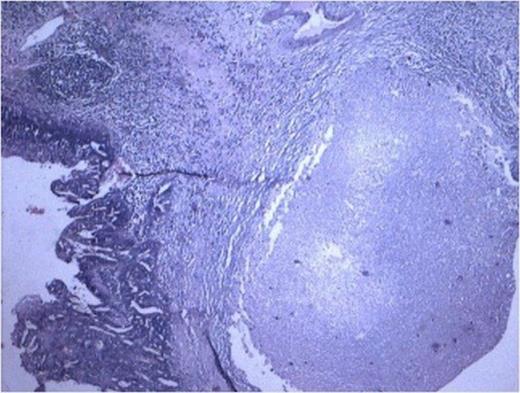

Histopathology from solid portions in pelvis region showed features of moderately differentiated squamous cell carcinoma (Fig 3). The tumor was not involving retroperitoneal soft tissue including renal vessels, Gerota’s fascia and lymph nodes.